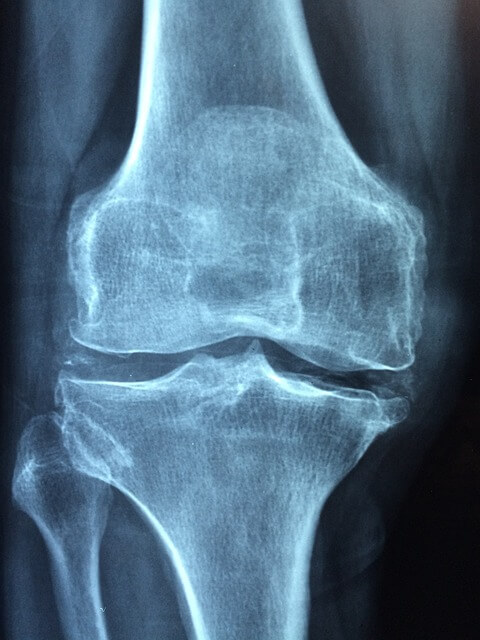

1. 관절 건강: MSM은 연골 형성 및 유지를 지원함으로써 관절 건강에 도움을 줍니다. 관절 통증과 염증을 완화하기 위해 그리고 쑤심과 붓기를 줄이기 위해 사용됩니다. 연구 결과 MSM이 동물 모델에서 관절염의 손상과 증상을 줄였다는 보고가 있습니다. 또한 인간의 경우 MSM을 복용하는 데 도움이 되는 것으로 나타났습니다.

5. 관절 통증: MSM은 관절 통증과 관련된 신경통증 및 염증을 완화하는데 효과적입니다. 관절 및 활동성을 개선하여 질병으로 인한 작업 부하와 통증을 줄이고 마디발증 치료에 유용하다고 알려져 있습니다.